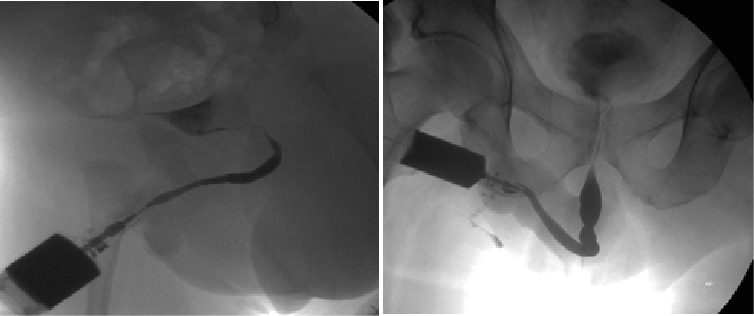

Retrograde urethrography is a very dynamic study, which must be taken into account when acquiring images, especially when sending still images, a common error is the leakage of contrast towards the skin (Figure 1) avoiding using a Foley catheter at the level of distal urethra to retain the contrast, however it can condition trauma [1]. Another common error is the ignorance of ideal projections for evaluation of the urethra (Figure 2), for example the Lauenstein projection, which is more useful for evaluating the hip. The imaging with a lack of contrast between the structures (Figure 3), which can be modified during and after the acquisition. It should be noted that on some occasions, in case of doubt, images will be taken from two different x-ray directions.

Figure 3: Lack of Contrast of the Structures, Either When Acquiring Them and Not Making Adjustments after the Process